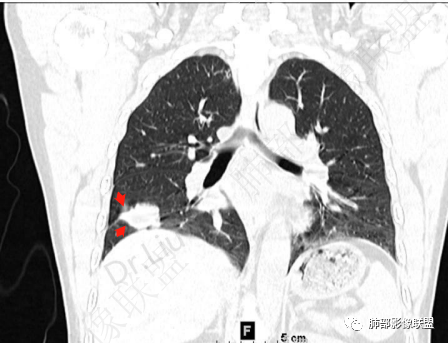

2、胸部CT右肺下叶胸膜下肿块性病变,边缘可见分叶毛刺、边缘膨隆,似有指状凸起,邻近胸膜稍牵拉凹陷,叶间裂以为不明显,提示收缩力较弱。近端支气管进入后截断,病灶内密度尚均匀,增强后可见轻度强化,未见空洞或钙化,并可见血管影进入。右侧肺门及纵隔内可见肿大淋巴结影。无胸腔积液。

3、综合患者临床症状及影像表现,需要考虑肿瘤性病变和非肿瘤性病变,肿瘤性病变需要考虑普通浸润性腺癌或结节型粘液腺癌、淋巴瘤、淋巴上皮瘤样癌、小细胞肺癌等,非肿瘤性病变主要考虑肺脑同病中的隐球菌。①普通浸润性腺癌,以肺外周多年、混合磨玻璃或实性结节/肿块,多见分叶、毛刺、胸膜凹陷、血管集束等征象,本例收缩力较弱、且强化偏轻,不够典型。②粘液腺癌,腺癌的特殊类型。多位于胸膜下(90%位于胸膜下,70%位于下叶胸膜下),边缘清或不清的GGO:提示粘液外渗,少数为纯GGO,缺乏中心纤维化区:毛刺、胸膜凹陷征少,很少胸膜侵犯,淋巴结转移少见,增强后无强化或低强化,本例病灶位于胸膜下,强化轻,收缩力弱,结节期粘液腺癌确实可以符合。③小细胞肺癌,吸烟男性多见,典型征象包括娘小崽大、腊肠样凸起、冰冻纵膈等,本例胸膜下病变大、但肺门淋巴结肿大程度较轻,不符合常见小细胞癌生物学行为,但有可疑指状凸起,小细胞肺癌不能完全除外。④淋巴上皮瘤样癌,少见的恶性肿瘤,患病年龄较轻,肿瘤多位于胸膜下,边缘多光滑,病灶周围可见磨玻璃,毛刺及分叶、胸膜凹陷少见,近端支气管可截断,增强多为中度-明显强化,本例除了强化程度偏轻外,影像表现基本可符合。⑤淋巴瘤,原发肺内淋巴瘤较少见,病灶多位于支气管血管束周围或胸膜下,密度多较均匀,边缘可膨隆也可平直收缩,可见支气管充气征、血管造影征等,强化多为轻中度,本例肺内结节血管穿行自然,局部有血管漂浮,长轴与支气管走行基本一致,肺门淋巴结肿大,不能排除。⑥隐球菌,影像表现可分为孤立结节型、大片实变型、多发结节或实变型、弥漫型。病变多位于胸膜下,边缘平直为主、可伴晕征,可见支气管穿行、部分可见支气管截断,密度多较均匀,部分可伴空洞,增强多为轻中度强化、延迟强化。本例病变位于胸膜下,收缩力弱,强化程度轻,但没有呼吸道症状,病变近端支气管截断,肺门淋巴结大,这些征象都难以用隐球菌解释,基本排除。

右肺下叶前基底段叶间胸膜下肿块,支气管边缘阻断,血管进入,轻度不均匀强化,胸膜牵拉,肿块胸膜侧见指状凸起(小细胞Ca常见),支持恶性特点,小细胞ca可能性大,结合肺肿瘤抗原和胃泌素释放肽前体检查,与腺ca鉴别,头痛史,建议补充颅脑CT检查排除转移瘤。